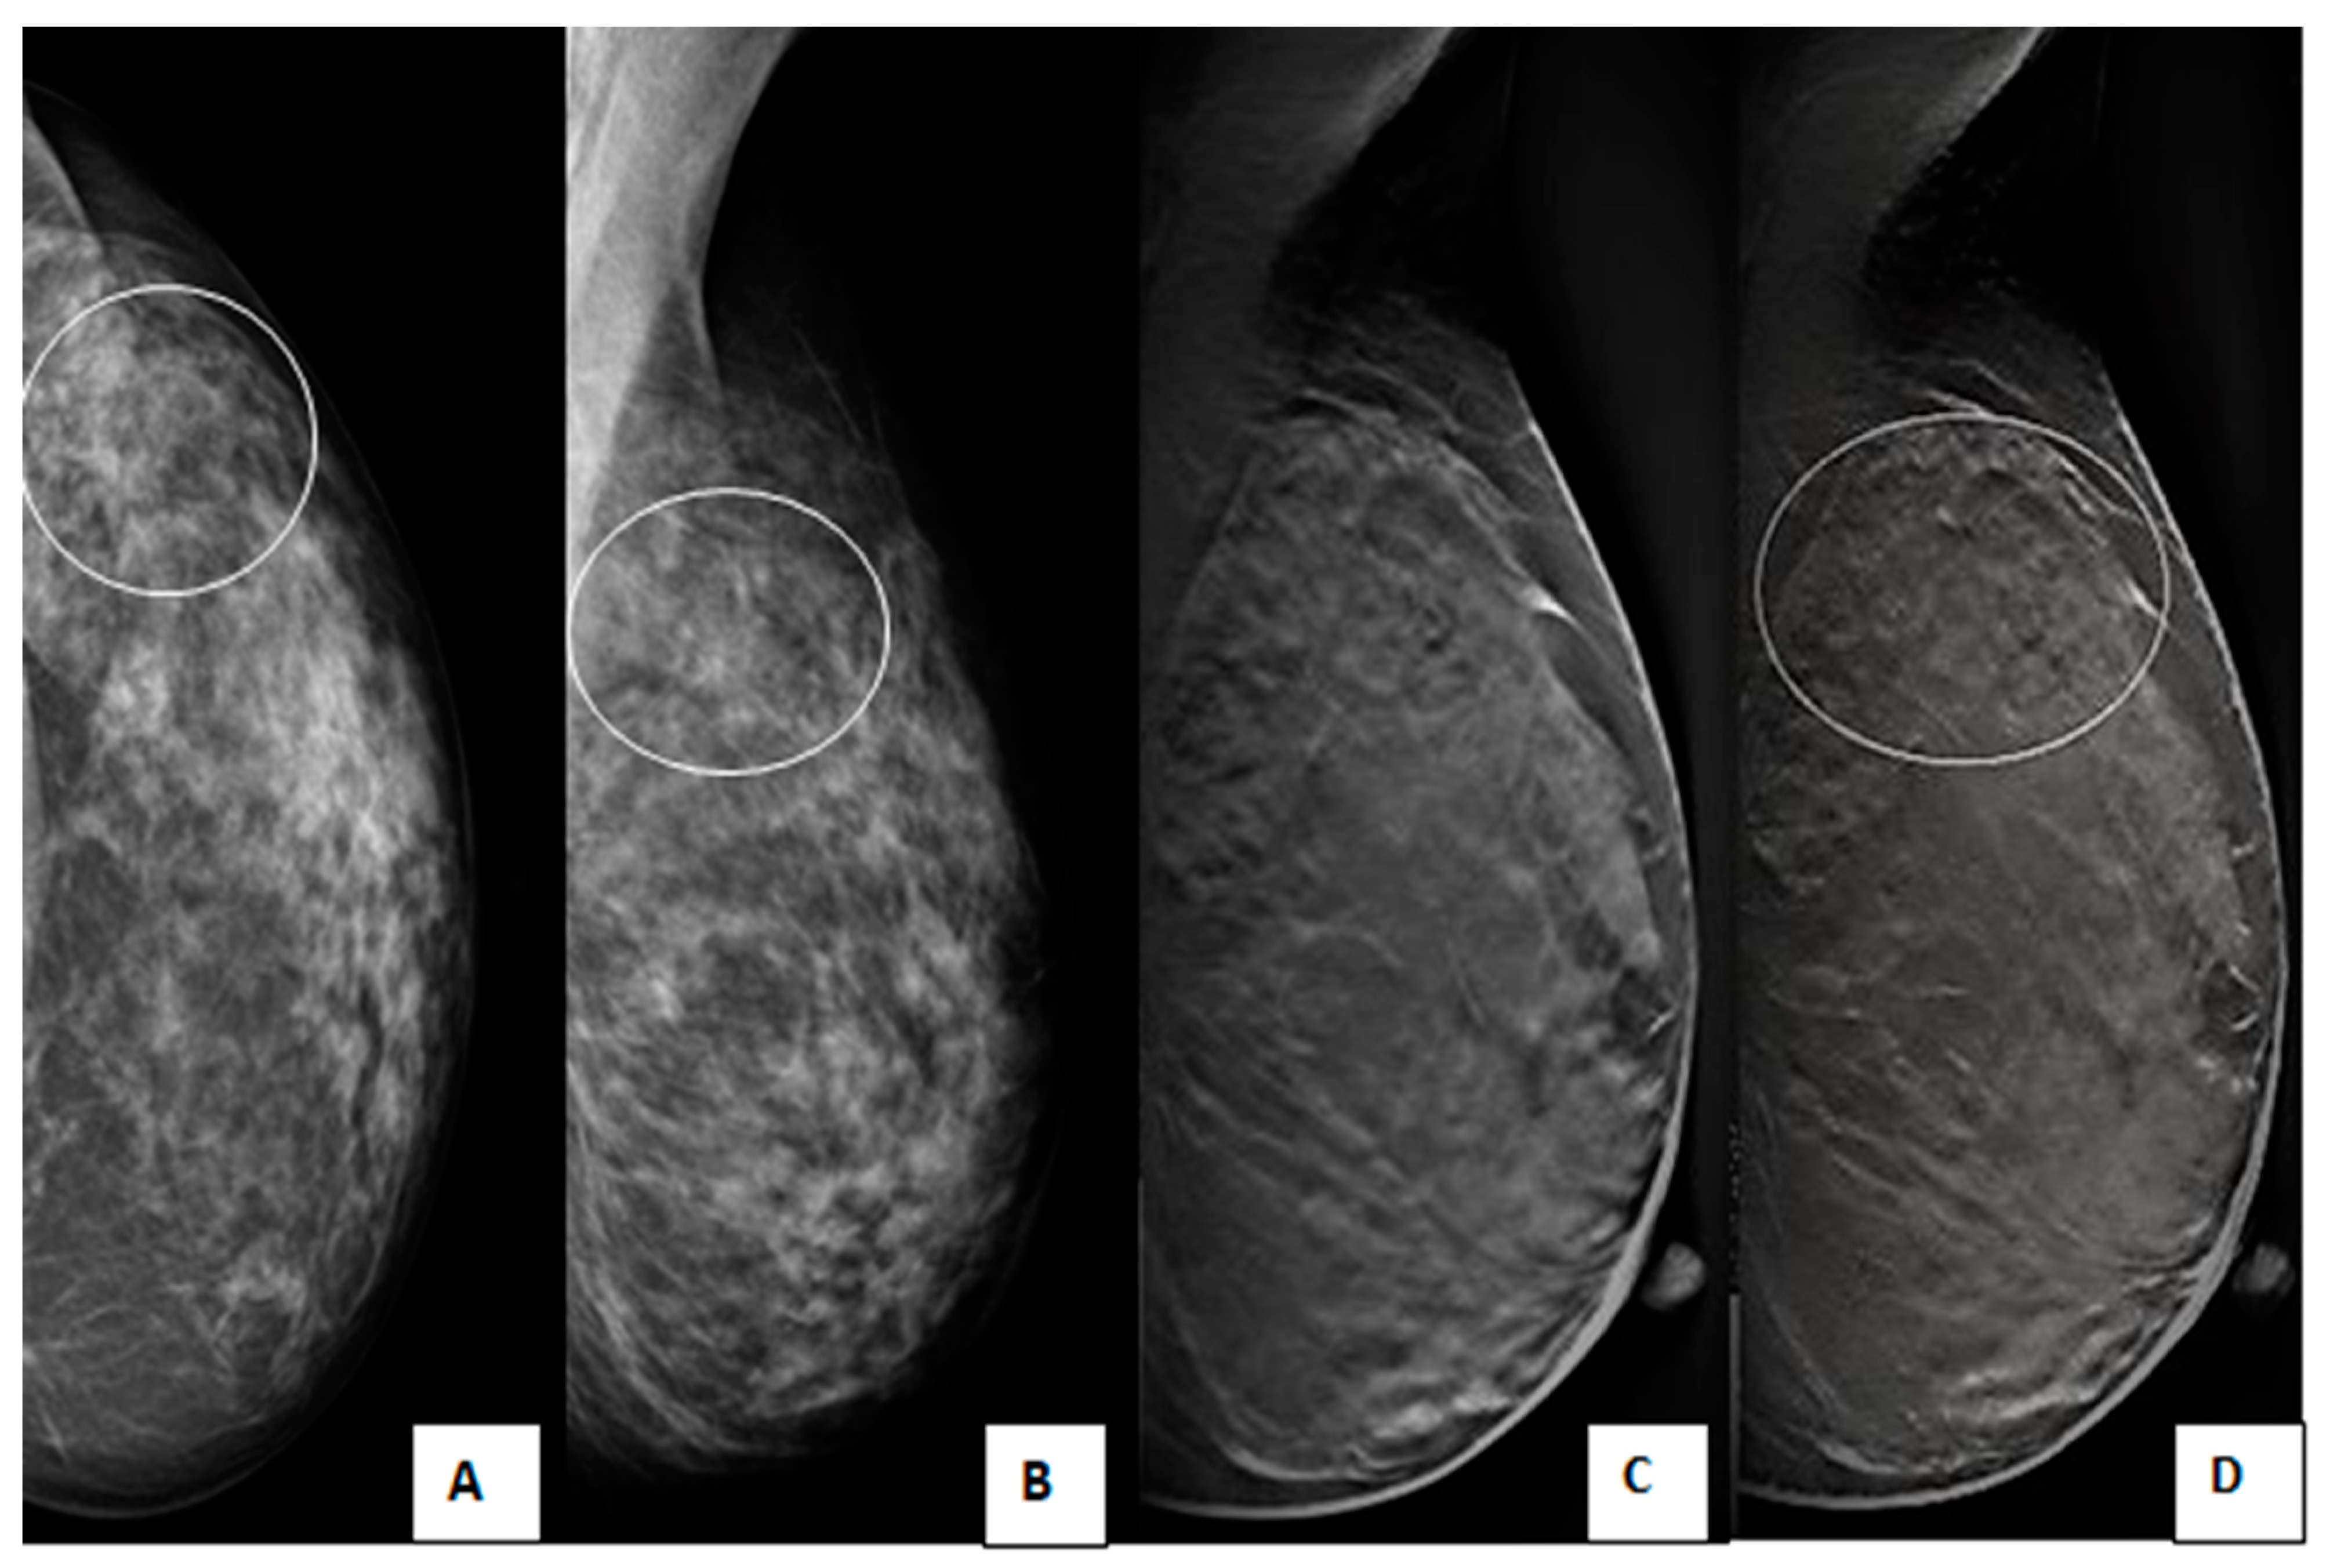

Figure 6. A 45-year-old female with a positive family history of breast cancer came for screening mammography. (A) Craniocaudal and (B) Mediolateral oblique DM images of the left breast show an upper outer quadrant speculated mass with obscured lower inner margin and surrounding architectural distortion (circles). (C,D) Mediolateral oblique DBT images of the left breast show an upper outer quadrant oval-shaped heterogeneous mass with circumscribed borders, but the lower inner margin is obscured (circles). The lesion was classified as BI-RADS 4a according to DM and downgraded to BI-RADS 3 according to DBT. Histopathological examination revealed invasive ductal carcinoma.